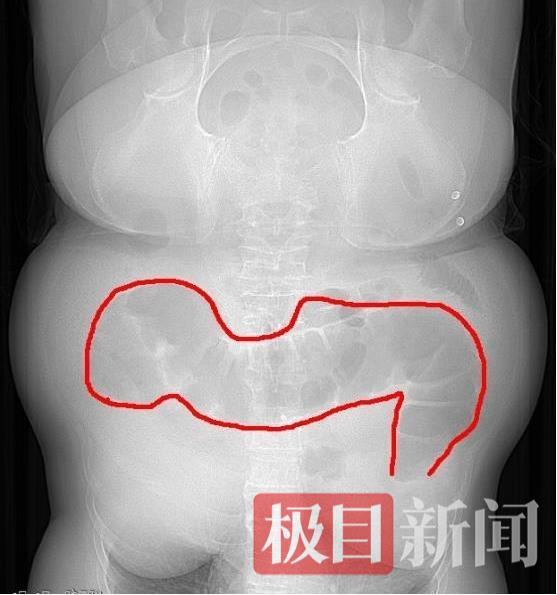

60岁的王女士5天没有排气排便,腹痛腹胀得痛苦不堪,被家属紧急送至家附近的湖北省中医院就诊。胃肠外科曹钧副主任医师、孙相钧主治医师会诊后,通过询问患者病史和查体,初步判断王女士为急性肠梗阻,病情危急,需要紧急解除肠梗阻。在迅速完善相关检查后,腹部增强CT提示:降结肠肿瘤导致的肠梗阻,肿瘤考虑恶性可能,升结肠及横结肠积气积便严重。

结肠扩张明显